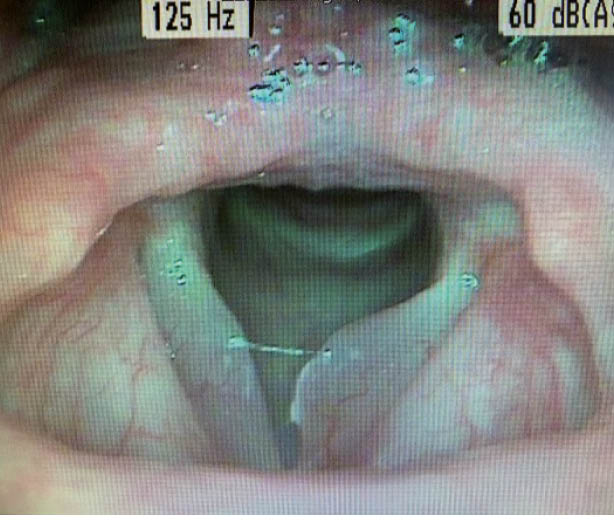

Bei unserer Patientin zeigte sich folgender laryngostroboskopischer Befund:

Bei dieser glasigen und glatten Schwellung der beiden Stimmlippen kann eindeutig die Diagnose eines Reinke-Ödems gestellt werden. Typische Patienten sind rauchende und kommunikative Frauen im Alter von 50-60 Jahren. Eine maligne Entartung muss nicht befürchtet werden. Für die Prognose ist das Sistieren des Nikotinkonsums wichtig. Bei geringem Leidensdruck oder Initialstadium kann mit logopädischer Stimmtherapie und Nikotinstopp eine gewisse Besserung erreicht werden, in den meisten Fällen ist jedoch eine phonochirurgische Abtragung in einer kurzen Narkose nötig. Insbesondere ist eine Abtragung indiziert, wenn es bei grossen Ödemen bereits zur Belastungsdyspnoe kommt.